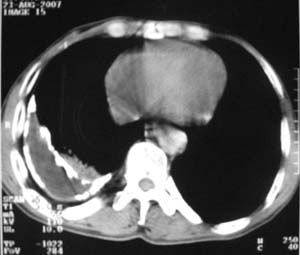

标题: CT9556:男,54岁,包裹性积液,请各位老师会诊其原因! [打印本页]

标题: CT9556:男,54岁,包裹性积液,请各位老师会诊其原因!

男,54岁,无任何不是感.体检发现右肺部阴影.现行ct进一步确诊.

包裹性积液伴胸膜钙化

右侧胸廓塌陷,肋间隙变窄,肋骨增生变粗,脏壁层胸膜肥厚、钙化。符合陈旧性结核性脓胸改变

右侧包裹性积液伴胸膜钙化.

结核性胸膜炎可能性大!脓胸!

包裹性积液伴胸膜钙化,结核性?

包裹性积液伴胸膜钙化,考虑结核性

右侧包裹性积液并胸膜钙化,性质还是结合穿刺细胞学检查的好,结核性、化脓性均会有钙化。

包裹性积液伴胸膜钙化,原因多种,国民一般为结核性居多